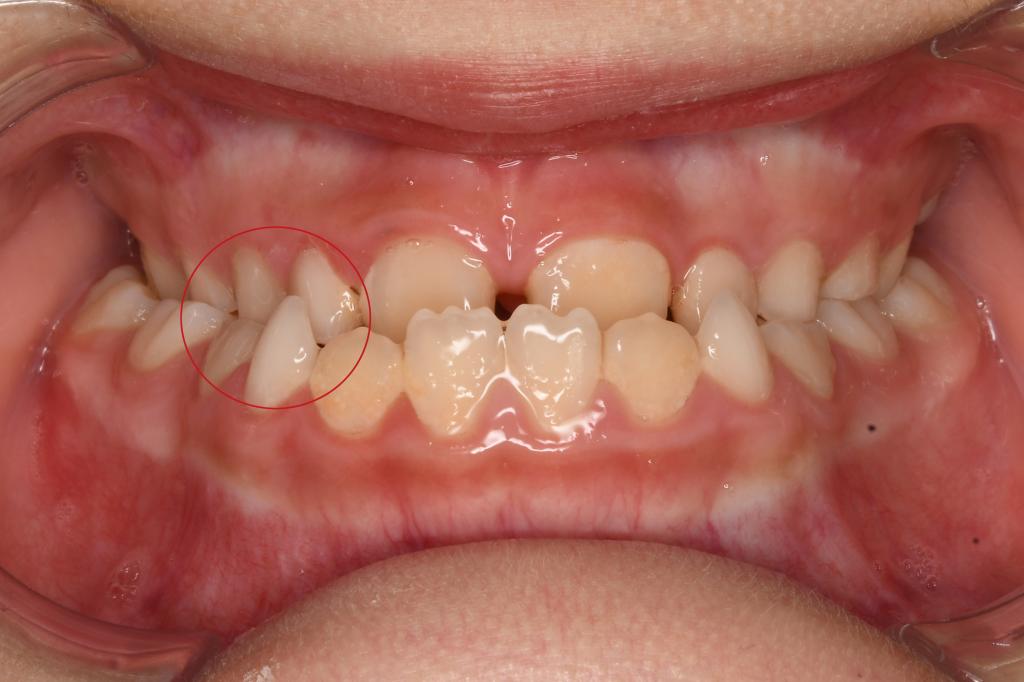

2. 后牙反合

后牙反合表现为下后牙咬在上颌后牙的外侧、上牙弓狭窄。单侧后牙反合患者会出现不同程度的颜面不对称,当上牙弓进一步狭窄时,会形成双侧后牙反合,影响其咀嚼。

矫治方法:后牙反合的患儿往往因为有龋齿而形成偏侧咀嚼的习惯,应及时治疗后牙区龋齿,纠正其偏侧咀嚼的习惯。乳牙列和混合牙列期的主要治疗方法主要通过调合以及扩展上牙弓宽度。常用的矫治器为Haas扩弓器和Hyrax扩弓器。